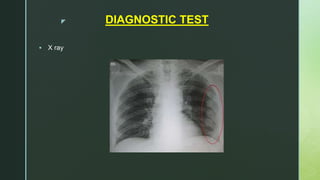

z DIAGNOSTIC TEST

 X ray